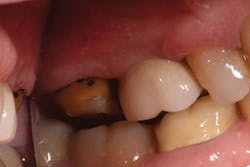

A 55-year-old female presented to my office for an evaluation of a crown placed on tooth No. 15 within the last few years. Her complaints included: "It feels big. I get a ton of food trapped in it, and it is kind of ugly." A bitewing was taken (Fig. 1) revealing an ill-fitting crown on No. 15. An intraoral photo was also taken (Fig. 2) confirming an oversized PFM with poor contours. The decision was made to remove and replace the crown.

FIG. 1